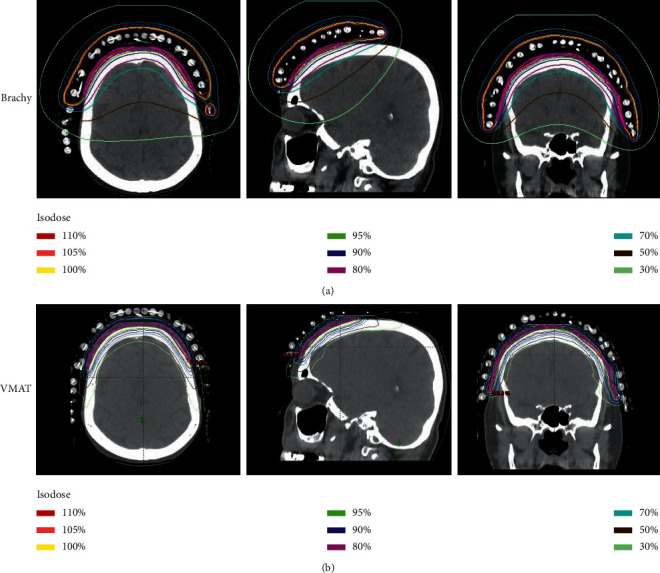

Purpose: Angiosarcoma of the face and scalp is a rare disease with high rates of recurrence. The optimal treatment approach is not well defined. This study presents a dosimetric comparison of high-dose-rate surface applicator (HDR-SA) brachytherapy to volumetric-modulated arc therapy (VMAT).

Methods: Between 2011 and 2018, 12 patients with primary or recurrent angiosarcoma of the face or scalp were treated with HDR-SA brachytherapy using CT-based planning at our institution. For comparison, deliverable VMAT plans for each patient were generated, and dose distribution was compared to the delivered HDR-SA brachytherapy plans.

Results: Both VMAT and HDR-SA brachytherapy plans delivered good coverage of the clinical target. However, the dose distribution of VMAT was significantly different from HDR-SA brachytherapy across a variety of parameters. Mean doses to the lacrimal gland, orbit, lens, and cochlea were significantly higher with HDR-SA brachytherapy vs. VMAT. Brain Dmax, V80%, and V50% were also significantly higher with HDR-SA brachytherapy.

Conclusions: There may be dosimetric advantages to VMAT over HDR-SA brachytherapy for many patients. However, individual tumor location, patient anatomy, and treatment reproducibility may result in HDR-SA brachytherapy being the preferred technique in a subset of patients. Ultimately, a personalized approach is likely to be the optimal treatment plan.